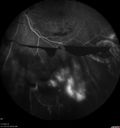

PDR and Vitreous Hemorrhage - High Risk Left Eye - Low Risk Right Eye369 views50 year old man with type I diabetes mellitus for 26 years. New Vitreous Hemorrhage in the left eye. Both eyes have NVE. Both also have foveal hypoplasiaMar 07, 2020